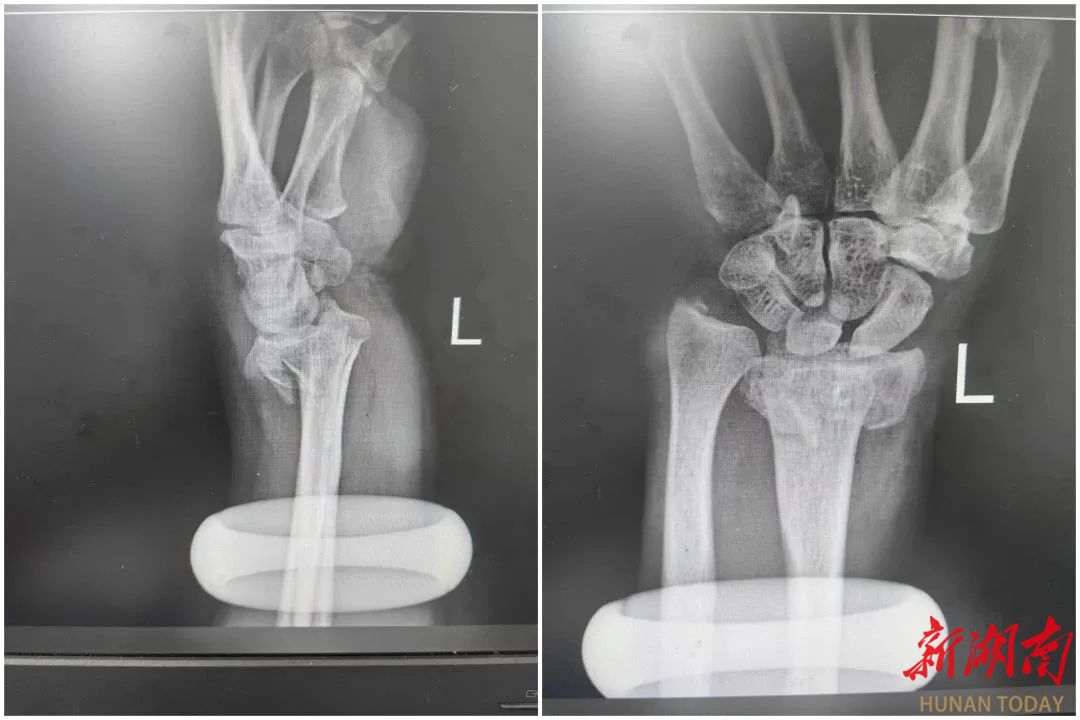

复位前

复位后